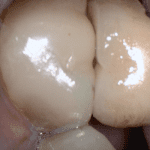

This case was scanned by two different scanners. Once by the Medit i500 and another time with the Aoralscan. Both the meshes are included so you can compare the two. It was scanned to deliver a case that retrofits a partial denture